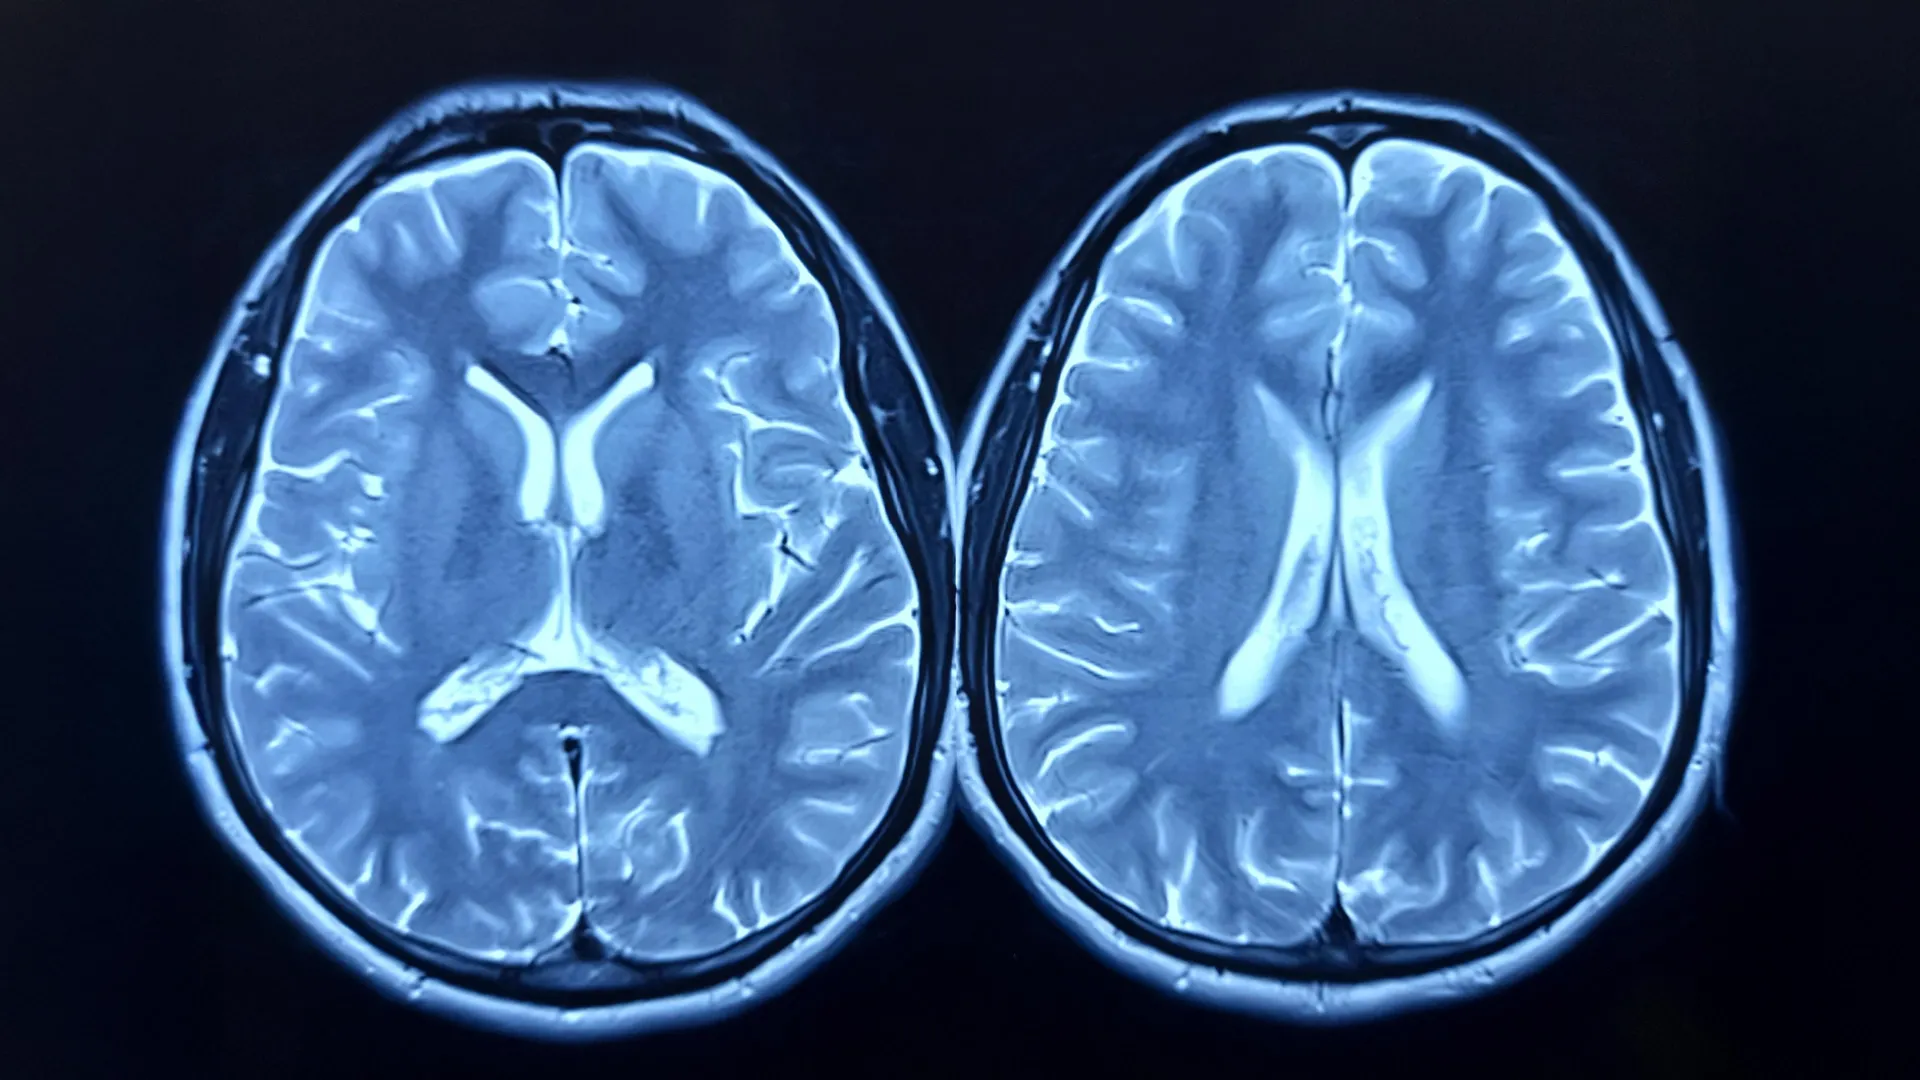

The research team looked at longitudinal brain scans from nearly 1,000 healthy adults, taken as part of the UK Biobank study. Some participants had scans before and after the pandemic; others, only before. Using advanced imaging and machine learning, the researchers estimated each person’s “brain age” — how old their brain appeared to be compared to their actual age.

The brain age model was developed using brain scans from over 15,000 healthy individuals, without comorbidities, allowing the researchers to build an accurate model for estimating brain age.

Stamatios Sotiropoulos, Professor of Computational Neuroimaging, and co-lead author added: “The longitudinal MRI data acquired before and after the pandemic from the UK Biobank gave us a rare window to observe how major life events can affect the brain.”